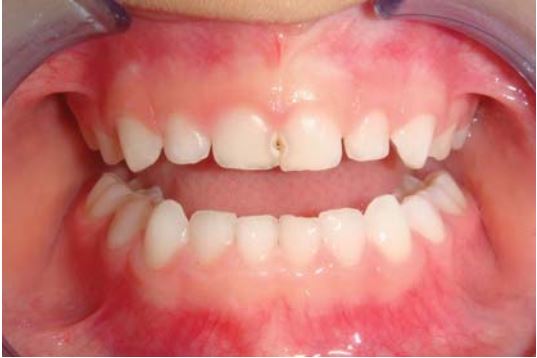

Sealant giúp ngăn ngừa sâu hố rãnh ở răng cối vĩnh viễn ở trẻ. Răng cối vĩnh viễn mới mọc thường xốp và dễ bị sâu. Men răng trưởng thành sau 62 tháng kể từ khi mọc. Trám sealant càng sớm càng giúp giảm tỉ lệ sâu hố rãnh. Nguy cơ sâu răng cao nhất là trong năm đầu tiên kể từ khi mọc răng.